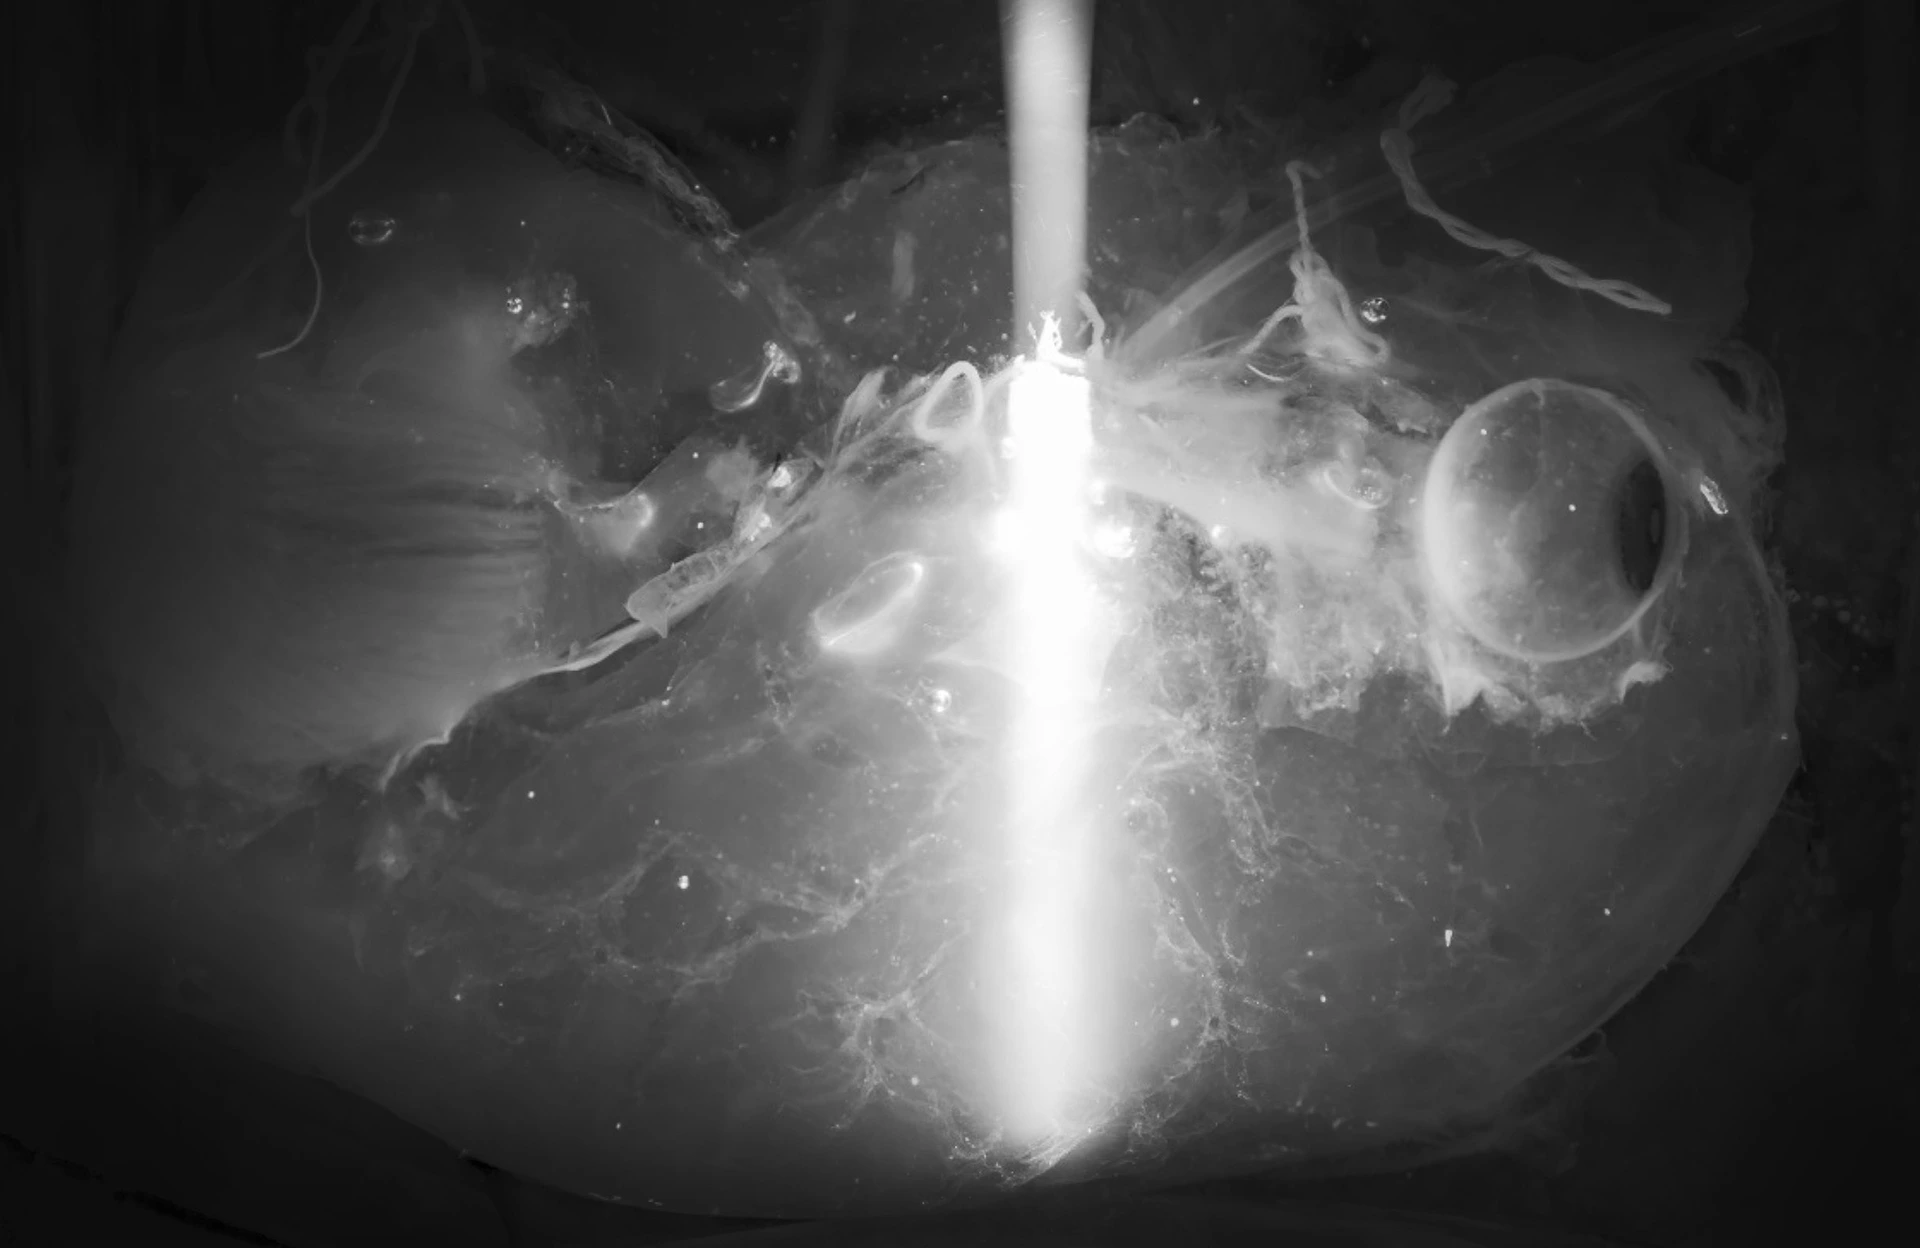

Kondensiertes Licht, das sich in einem transparenten menschlichen Gehirn von einem Ende zum anderen bewegt.